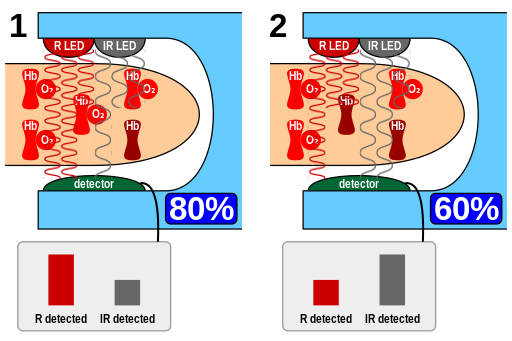

Hypoxemia – is a condition involving abnormally low blood oxygen levels. It can lead to bluish skin, difficulty breathing and fast heart rate. Apart from sleep apnea and higher altitudes, hypoxemia can be also be caused by many underlying illnesses, mainly lung and heart related especially in conditions of low environmental oxygen, diffusion impairment, hypoventilation, right -to left atrial shunting (image below).

Hypoxia – is a condition involving abnormally low levels of oxygen in body tissues. It can lead to bluish skin, confusion, difficulty breathing, restlessness and fast heart rate. Hypoxia is different to hypoxemia as hypoxia is low oxygen levels in tissues whereas hypoxemia is low oxygen levels in blood.